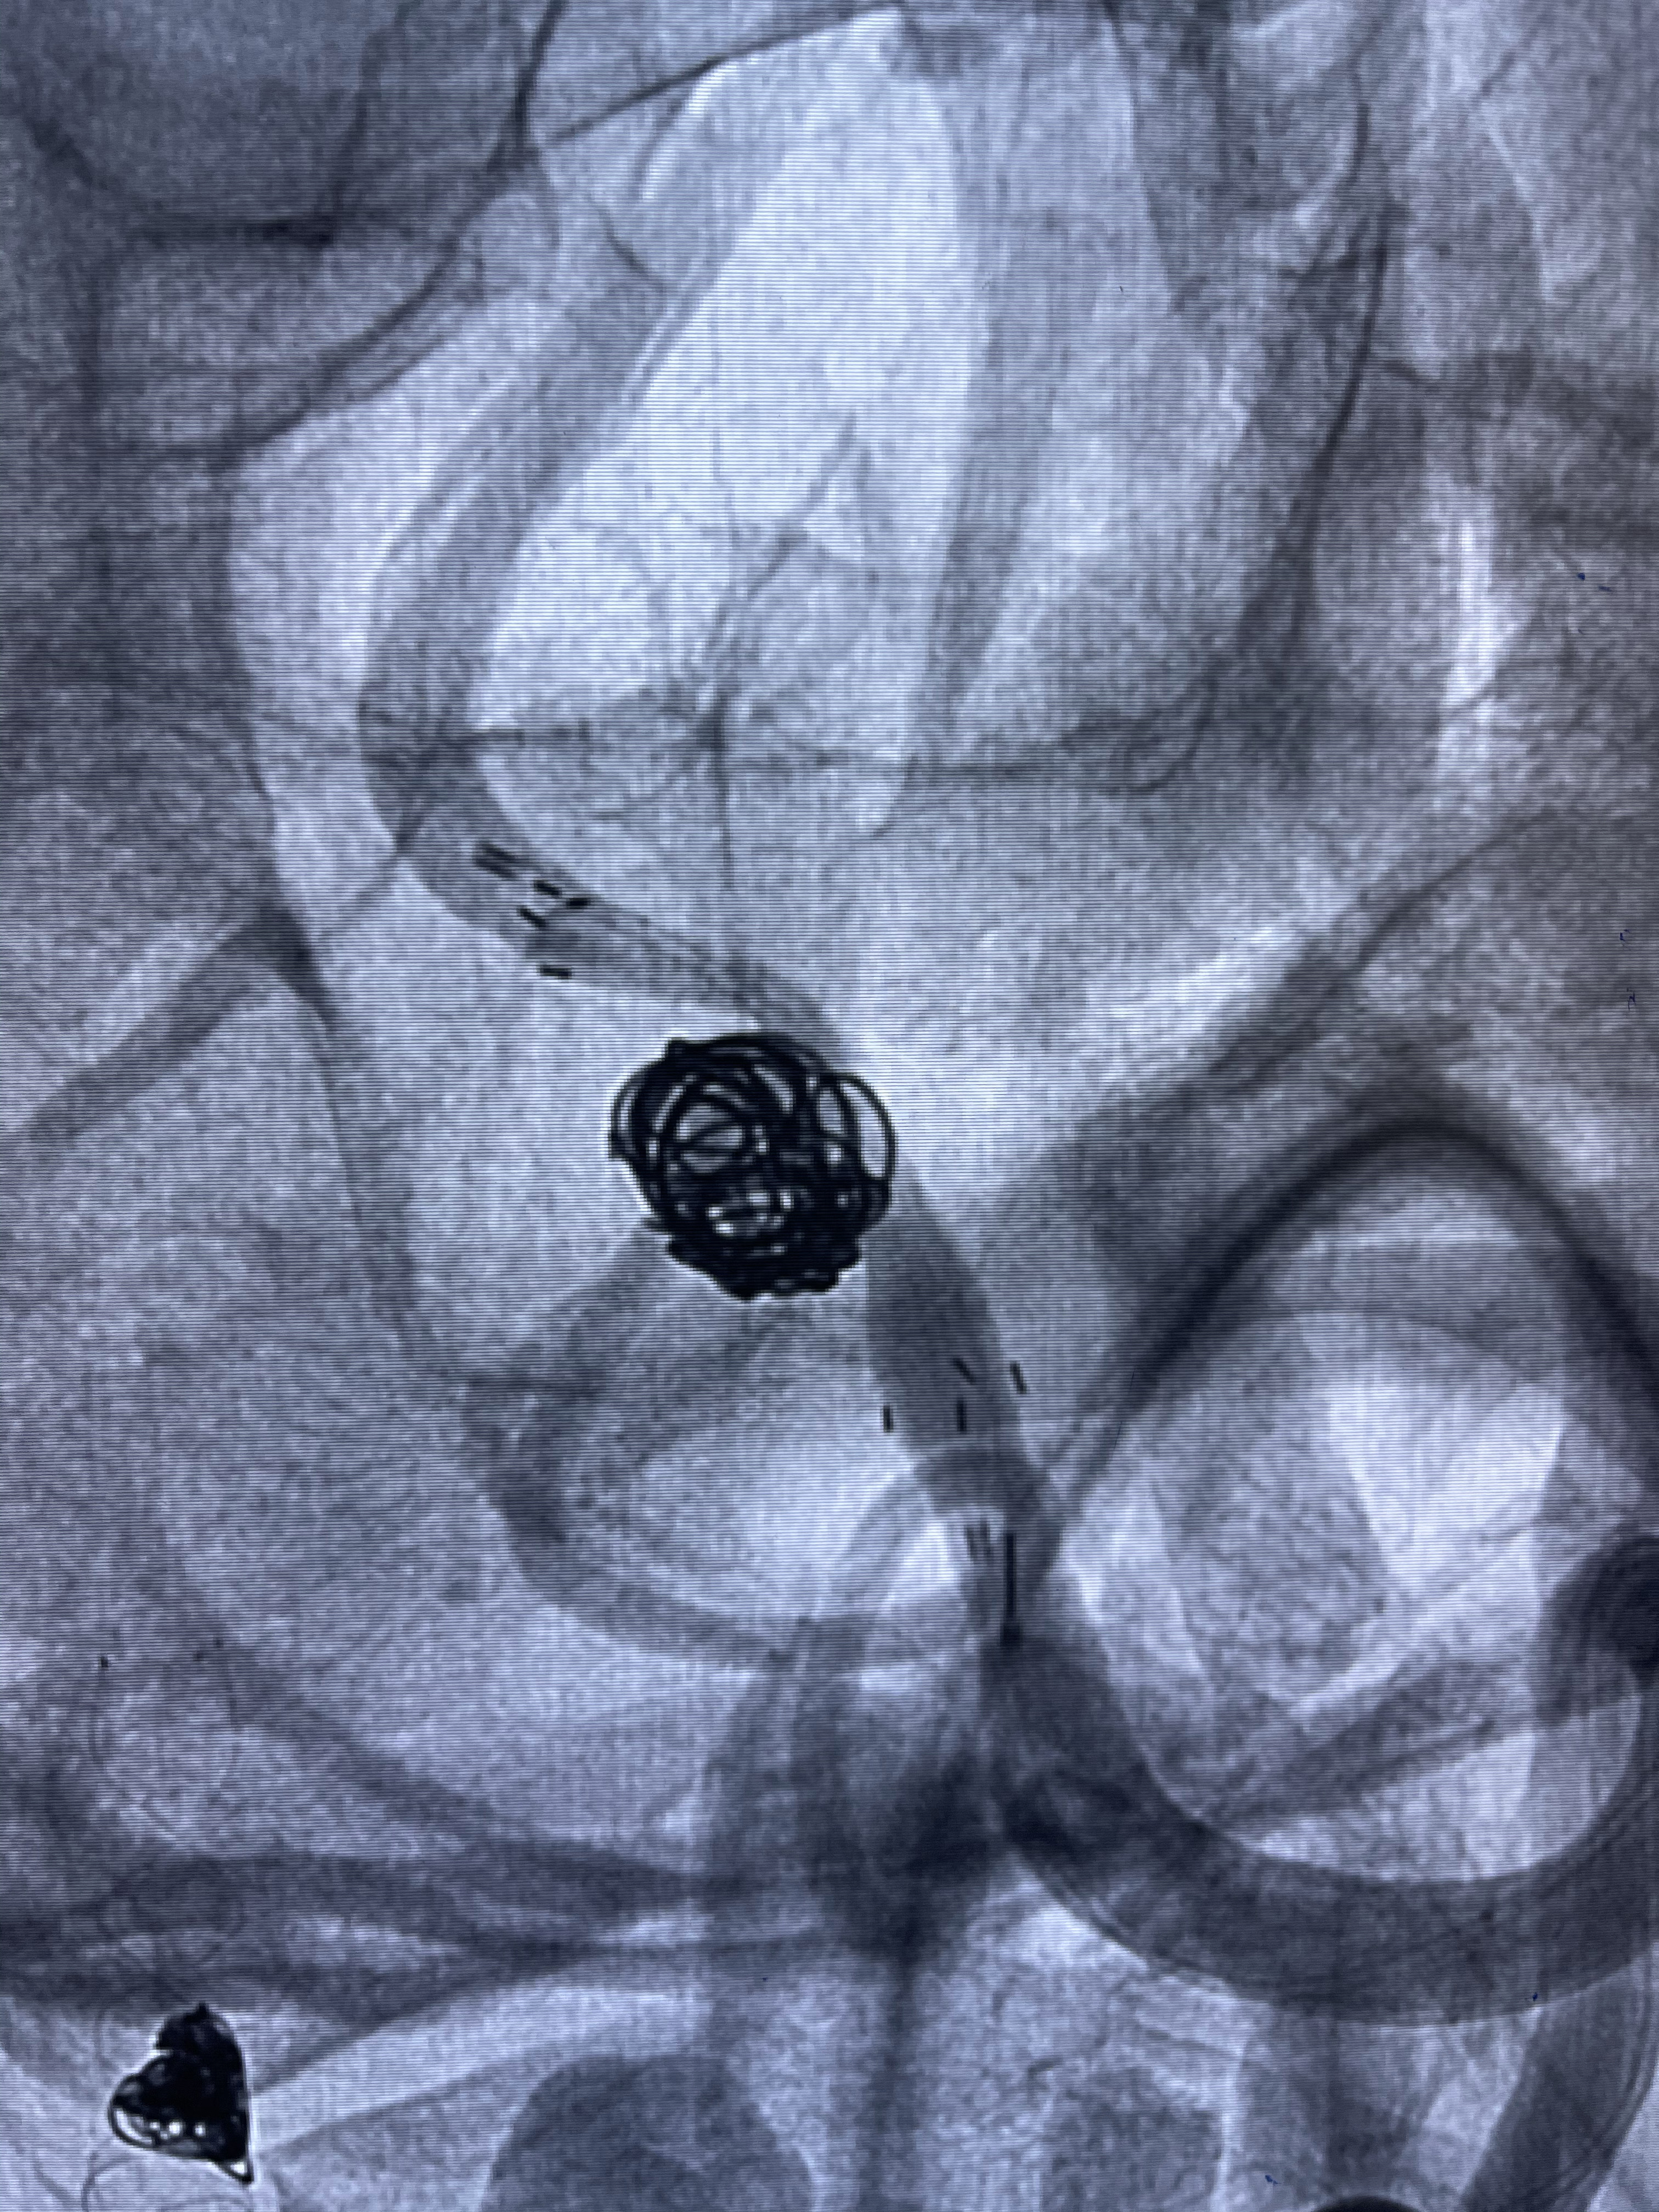

即刻造影

支架到位